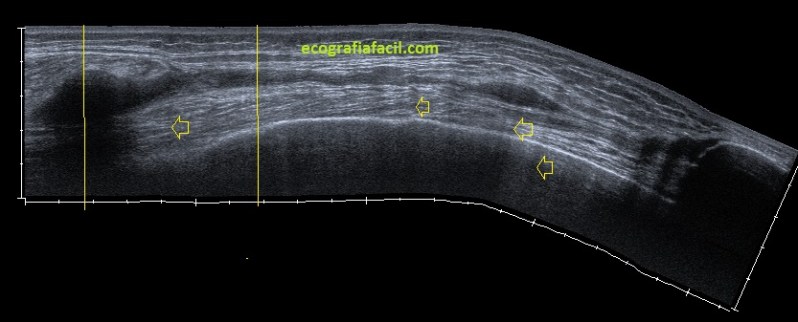

En la imagen 5 ves una estructura con un campo de escaneo limitado a la zona de interés, de derecha a izquierdo de la pantalla o de proximal a distal según la zona a estudio unos 5 cms, que es el tamaño del transductor. La anatomía de la ecoestructura perfectamente delimitada y nítida.

En la imagen 6 ves que la estructura estudiada es de casi 25 cms, sumados, donde la reconstrucción de la imagen hace que sea más pequeña y todo esté más junto de superficial a profundo, emborronándose todo o perdiendo nitidez. En la imagen 6 ves un tramo marcado con líneas amarilla finas correspondiente al mismo tramo de la imagen 5, observa tu misma la diferencia, la diferencia es sustancial. Las flechas amarilla corresponden a sombras acústicas por la sumación de la imagen unido al movimiento del operador y eventualmente a alteraciones del tejido (calcios) de la ecoarquitectura que se verán acentuados.